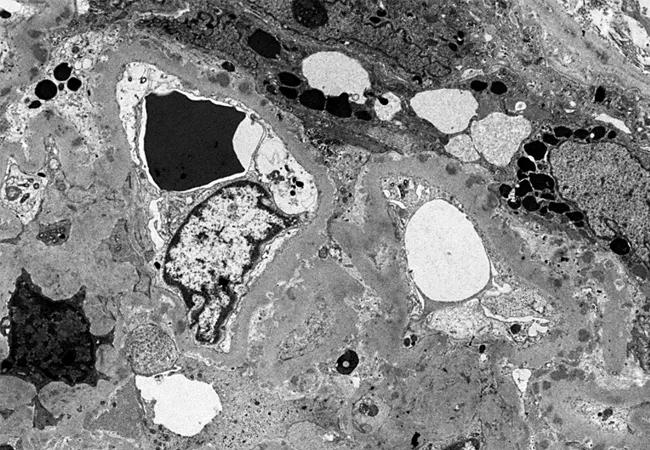

Electron microscopy of glomerulus from patient with lupus